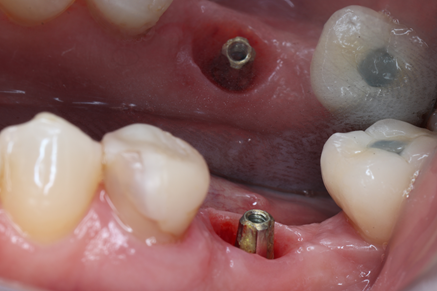

A cirurgia foi realizada com fresagem a 600 RPM e fresagem convencional utilizando como fresa final a fresa do diâmetro do implante, devido a necessidade de ativação desse implante de forma precoce, seguindo assim o protocolo recomendado pelo fabricante. O torque no momento da instalação do implante foi de 25 Ncm, permitindo assim, um maior aproveitamento das câmaras de cicatrização. Na própria etapa cirúrgica foi realizada a instalação do pilar Ideale 3.3 X 4 X 1.5 apenas com força digital e foi realizado a confecção de um cicatrizador personalizado.

Após 28 dias da cirurgia, a paciente retornou, o pilar Ideale foi torqueado e foi realizado o escaneamento intraoral com o iTero para confecção da prótese definitiva.